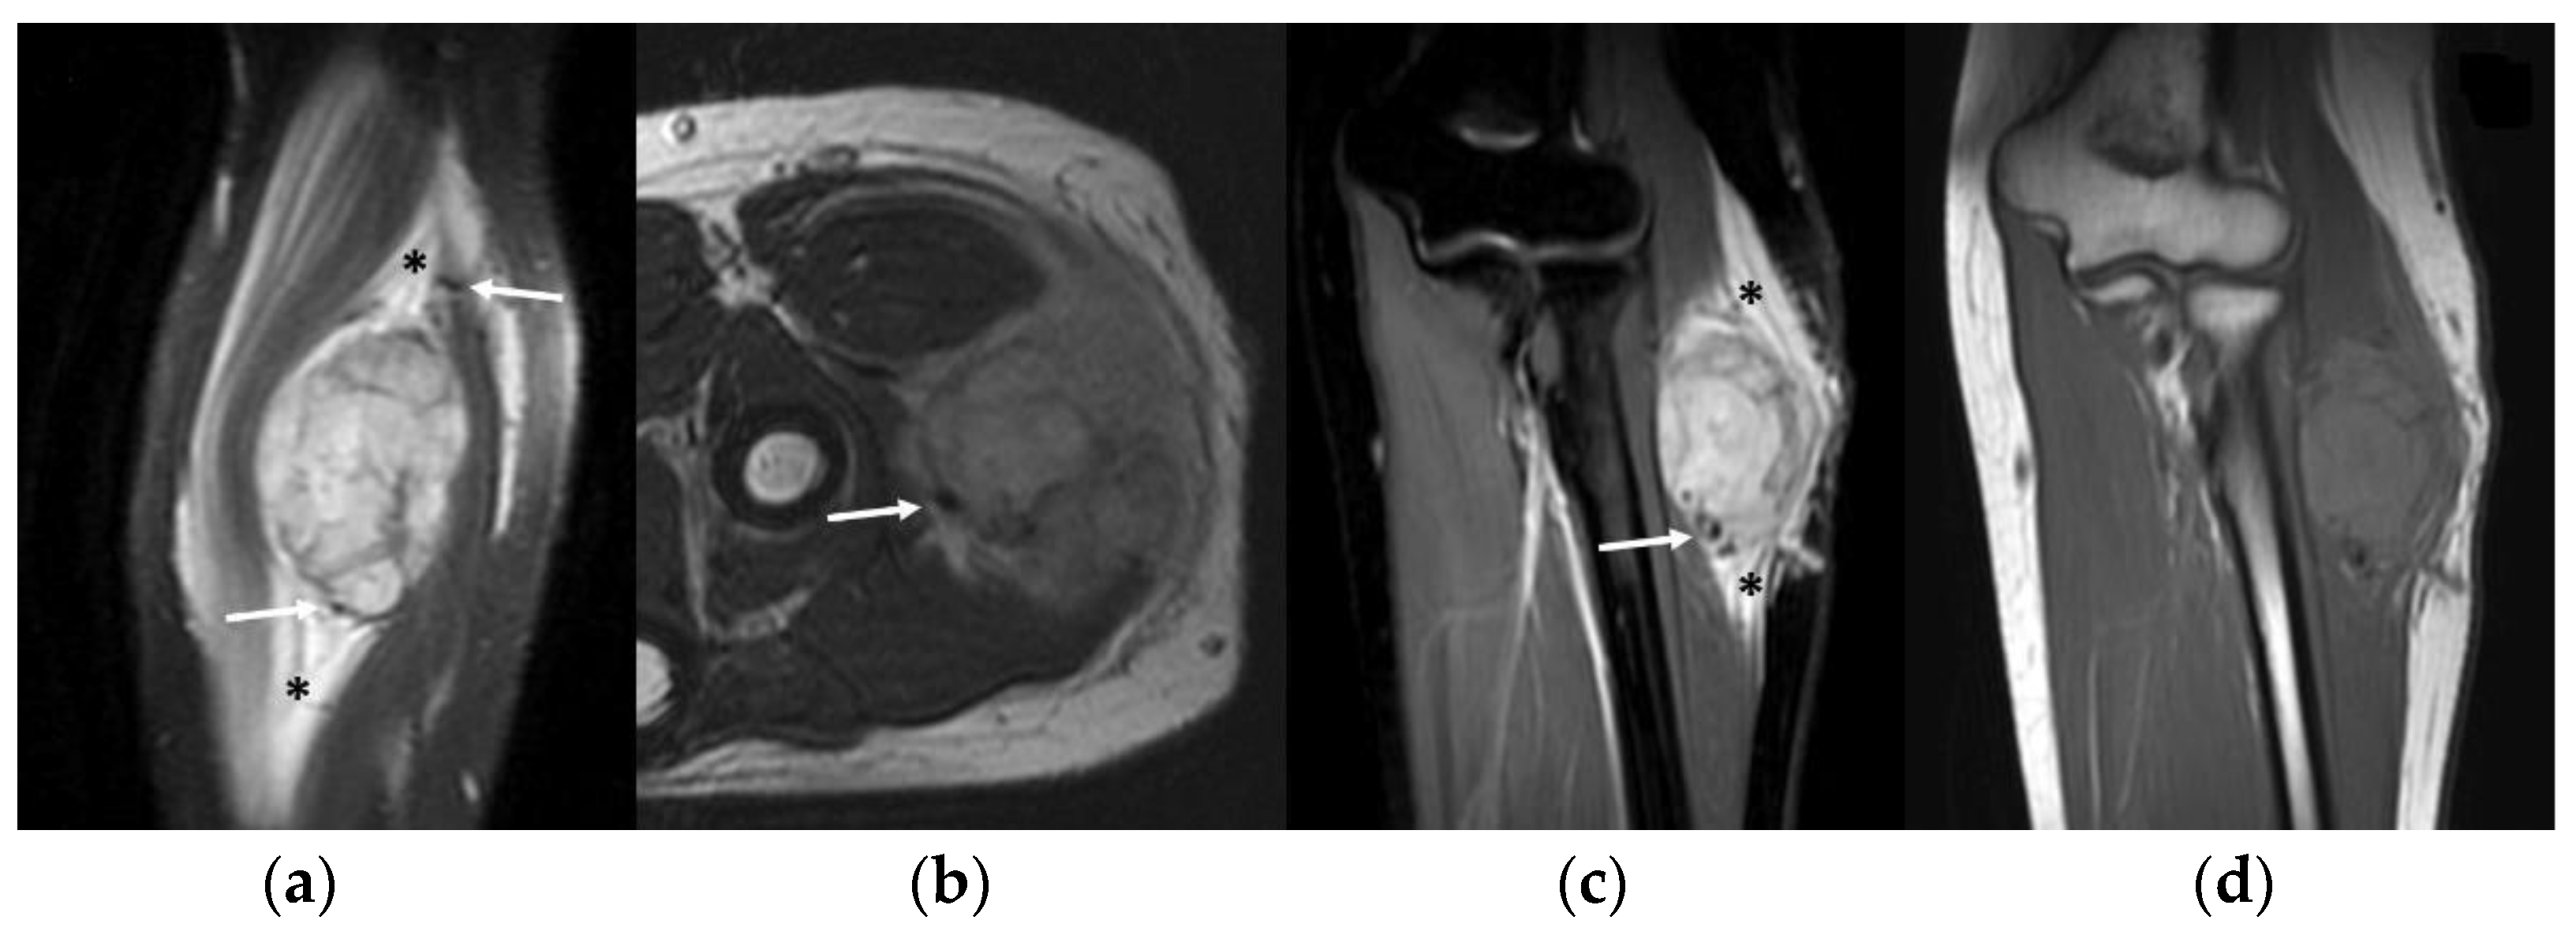

3.4. MRI Features

- Slight hyperintense MRI signal on T1-WI and a moderately inhomogeneous hyperintense signal on T2-WI

- MRI flow voids on fluid-sensitive sequences

- MRI peritumoral edema

| Deep-seated location | Well-defined borders | Intra and peritumoral flow-voids | Low density on unenhanced scans |

| Peritumoral feeding vessels | Inhomogeneous hypoechoic pattern | Slightly high SI on T1w | - |

| Strong internal vascularization | Arteriosus Doppler sonographic pattern inside peritumoral vessels | High SI on T2w | - |